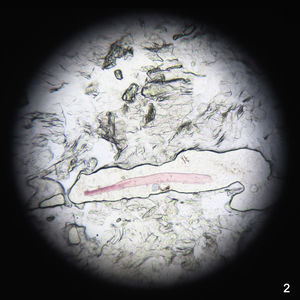

CasosNiña de 3 años de edad, sin antecedentes patológicos de interés, que presentaba de forma espontánea varias máculas hiperpigmentadas asintomáticas localizadas en la frente y región temporal de 4 meses de evolución (fig. 1A). Eran lesiones no descamativas, con signo de Darier negativo y sin antecedente previo de inflamación en el área afecta. El resto del examen físico no evidenció otras alteraciones. Su hermana de 2 años, diagnosticada de dermatitis atópica, presentaba máculas de similares características en la misma localización (fig. 1B). El inicio de las lesiones había coincidido en ambas niñas, durante los meses de invierno. Se investigaron probables factores desencadenantes sin obtenerse ninguna sospecha relevante. El resto de los miembros de la familia y contactos más cercanos no presentaban lesiones. Se realizó test de celo sin observarse estructuras sugestivas de micosis superficial. En la superficie del celo, se encontraron restos de estructuras fibrilares de coloración rosada que con luz polarizada tenían un aspecto fibrilar sintético (fig. 2). Tras 12 meses de seguimiento, ambas niñas presentaban un buen estado general, sin síntomas sugestivos de compromiso sistémico y con persistencia de las lesiones.